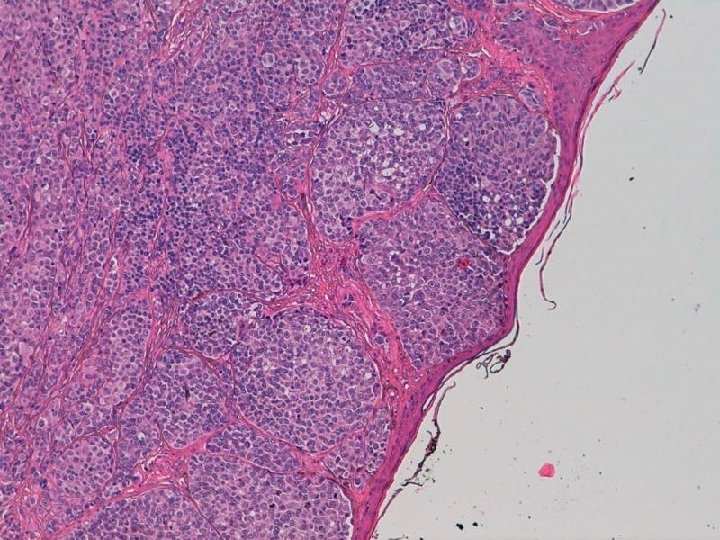

DIAGNOSTICO Melanoma dérmico originado sobre nevus melanocítico preexistente Tipo Miescher, no ulcerado, Nivel 4 de Clark, breslow de 1, 92 mms.

• La asociación o coexistencia de nevus y melanoma maligno se ha descrito frecuentemente. • El melanoma surgido melanocítico infrecuente. de un nevus intradérmico es muy

• Únicamente 4 casos descritos desde 1962. • En 3 de los 4 casos publicados el componente de melanoma maligno se desarrolló debajo de los nidos de células névicas. • En uno de los casos las células de melanoma maligno se encontraban entremezcladas con las células névicas.

En el presente caso se observa la particularidad de que el componente de nevus se localiza lateralmente al melanoma y en continuidad con éste.